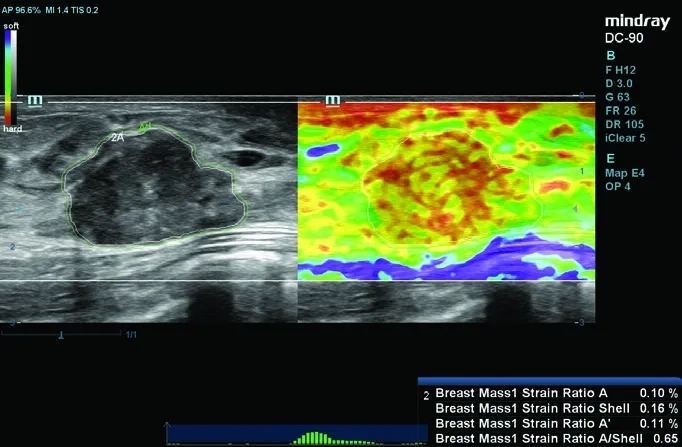

• Natural Touch Elastography — ПО для оценки эластичности тканей методом компрессионной эластографии;